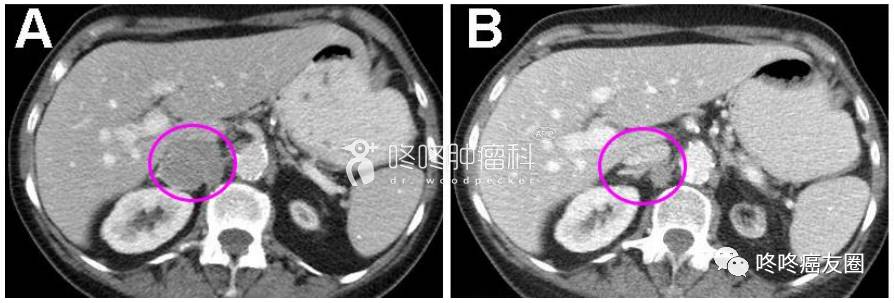

一位患者用药前后的CT图像对比,肿瘤明显缩小。